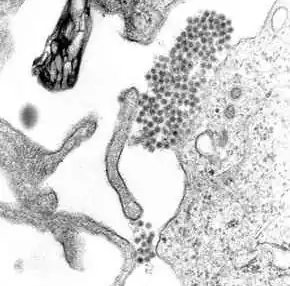

A transmission electron microscopy image showing dengue virus

A TEM micrograph showing dengue virus virions (the cluster of dark dots near the center)

Dengue fever virus (DENV) is an RNA virus of the family Flaviviridae; genus Flavivirus. Other members of the same genus include yellow fever virus, West Nile virus, Zika virus, St. Louis encephalitis virus, Japanese encephalitis virus, tick-borne encephalitis virus, Kyasanur forest disease virus, and Omsk hemorrhagic fever virus.[31] Most are transmitted by arthropods (mosquitos or ticks), and are therefore also referred to as arboviruses (arthropod-borne viruses).[31]